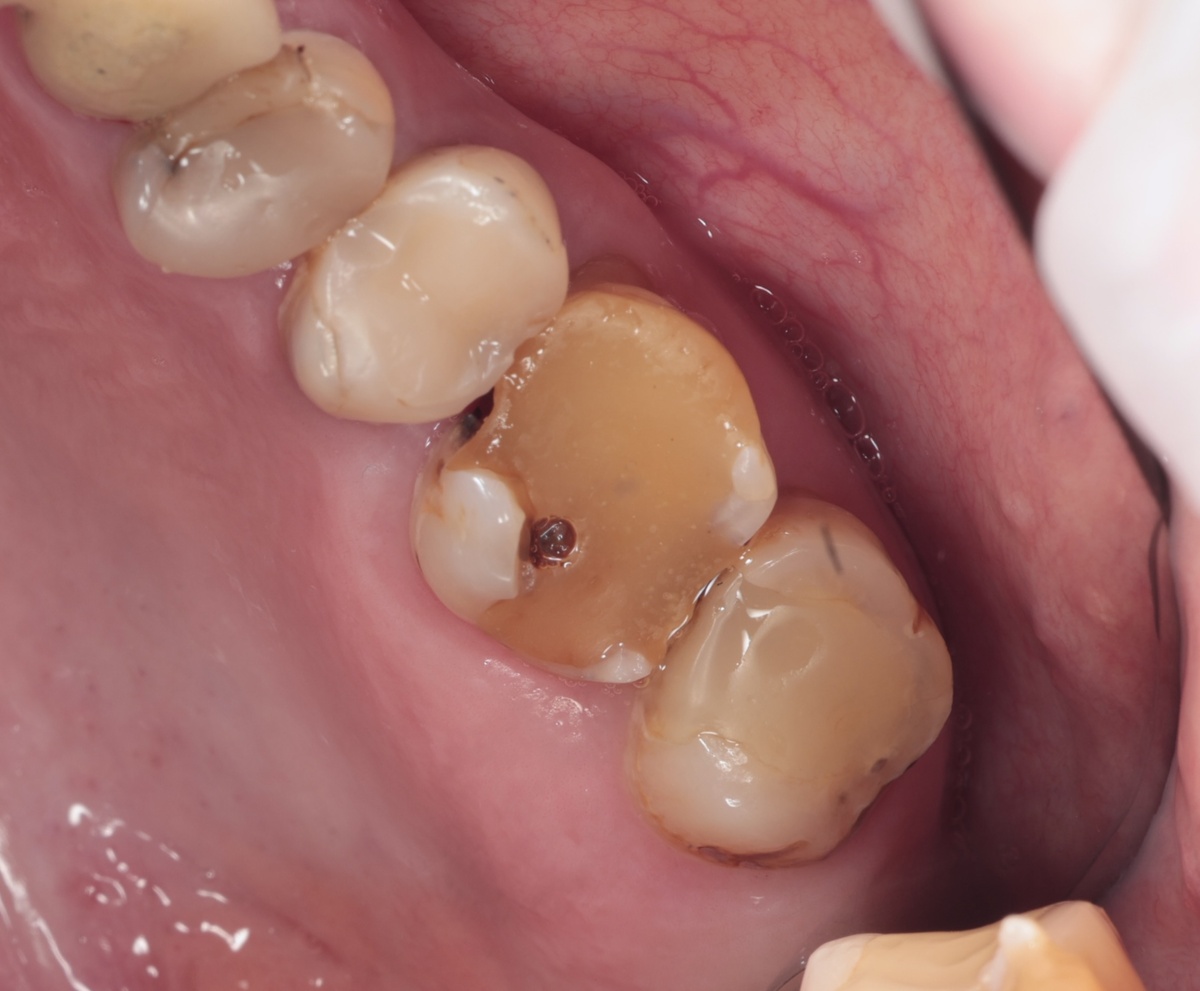

До "нерва" кариозный процесс почти добрался, очень глубоко. На жевательной поверхности стояла объемная старая пломба:

Дефектная пломба с акерным штифтом

Пациентка рассказала: несколько лет назад другой врач уже осматривал этот зуб и он ему не нравился. Вердикт был однозначным - лечению не подлежит. Ждите, пока заболит, тогда удалим. Всё, иного не предусмотрено.